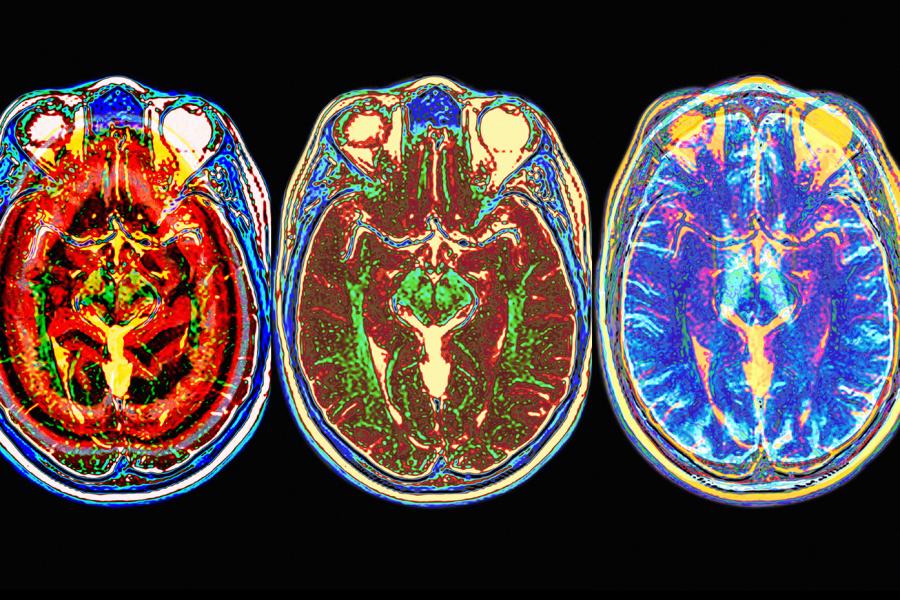

A lo largo de los últimos 20.000 años el cerebro humano se ha reducido aproximadamente en el tamaño de una pelota de tenis. Este es un descubrimiento notable porque durante la mayor parte de nuestra evolución nuestro cerebro se había ido haciendo cada vez más grande. Tampoco asociamos un cerebro que está encogiéndose con los avances en ciencia, tecnología, educación y demás. Nuestro estereotipo es que los científicos sabios tienen grandes cerebros. ¿Por qué iba a empezar a encogerse el cerebro humano de repente, después de haber estado expandiéndose durante la mayor parte de su evolución?

Un posible mecanismo para explicar los cerebros más pequeños sería que los individuos que son más pasivos tendrían niveles más bajos de testosterona. La testosterona se asocia con agresividad y dominancia pero también tiene propiedades anabolizantes haciendo los órganos y músculos más grandes. También aumenta el tamaño cerebral. En sujetos que se hormona para cambiar de sexo se ha observado que su cerebro aumenta o disminuye también de tamaño, según las hormonas que estén tomando (andrógenos o estrógenos).